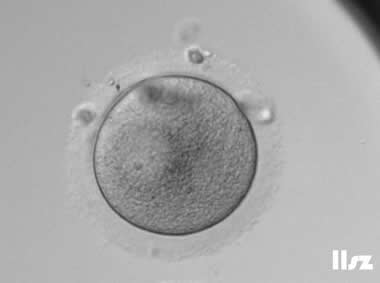

3. 成熟卵母细胞(MII)及其COCs(正常COCs)

卵细胞呈现规则的圆形且颜色较浅,放射冠完全分散,颗粒细胞团较大,排列稀疏。成熟卵母细胞一般在取卵后体外培养2-6小时再行授精。

|  |

| 0小时COCs的MII卵(4x) | 0小时COCs的MII卵(10x) |

|  |

| 2小时COCs的MII卵(10x) | 4小时去颗粒细胞后的MII卵(10x) |